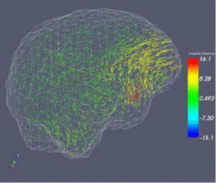

| R01HL116931 Airway Inspector: a chest imaging biomarker software platform for COPD

Airway Inspector is a open source software tool based on Slicer 2.x developed at Brigham and Women’s Hospital for the analysis of chest CT scans for the analysis of emphysema and airway disease. The tool was conceived to analysis low resolution CT scans bringing the gap between retrospective data and new emerging CT technologies. The success of the tool in the COPD clinical community is supported by the array of peer-review publications that have used the tool to define metrics of disease that enable hypothesis driven research. Beside the existence of alternative commercial applications, Airway Inspector is the only freely available maintained platform for COPD research. In spite of its success, Airway Inspector is limited to a discontinued version of Slicer. The broad objective of this proposal is to support the refactoring and development of Airway Inspector as a platform for image-based COPD research. This goal will be achieved by the creation of the Chest Imaging Biomarker Platform (CIBP) library that integrates novel algorithm solutions to lung image analysis that have been developed in our laboratory. Those solutions include: robust lung extraction, parenchymal tissue classification based on local density, airway, fissure and pulmonary vascular extraction based on scale-space particles and airway labeling based on Hidden Markov Models. That software platform will be used to create workflows that will be integrated in Slicer 4 for their deployment in the clinical community. The workflows will provide an end-to-end solution for the clinical to obtain phenotypes to characterize emphysema, airway disease and pulmonary vascular remodeling. Pending Council Review Funding Duration: 12/1/2012 - 11/30/2017 | |

| NAMIC supports COPDGene® quantitative analysis The Genetic Epidemiology of COPD (COPDGene®) Study is one of the largest studies ever to investigate the underlying genetic factors of Chronic Obstructive Pulmonary Disease or COPD. Through the enrollment of over 10,000 individuals, the COPDGene® Study aims to find inherited or genetic factors that make some people more likely than others to develop COPD. With the use of CT scans, COPDGene® also seeks to better classify COPD and understand how the disease may differ from person to person. Funding Duration: 09/27/2007-07/31/2012 | |